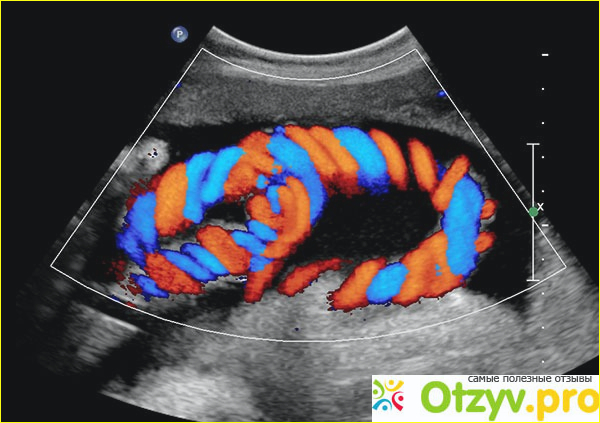

С этими болячками прям жизнь не мила, и к этим докторам ходить уже совсем не хочется. Только эти анализы ходишь сдаёшь для чего не понятно, толку то всё равно нет никакого. И вот тоже обследование не из дешёвых доплеровское исследование кровотока, но сказали очень хорошие и тогда можно лучше понять что определённо со мной. Мне порекомендовали сделать цветовой, очень хорошее исследование на котором видно или можно обнаружить работу сосудов. Значит голова у меня кружится из за проблем с сосудами, только интересно можно ли как то это всё исправить. Залезла в интернет посмотреть что это за доплеровское обследование, цветное чем хорошо что всё понятно и предельно ясно. Также цветовой и энергетический доплер помогает определить и разделяет на части, то есть достаточно глубокое и исследование обнаружить кисты и опухли, поскольку внутреннее содержимое кисты не имеет сосудов и поэтому картина изображения сможет это отметить. Не разобрать цветовое изображение, что к чему и как но красным цветом это кровоток к датчику, а от датчика синим, что означает без медицинского образования не понять. Турбулентный кровоток это я так понимаю, в этой зоне определённо находится кровеносный застой и на изображении он котируется сине-зелёно- желтым цветом. Цветовой доплер используется для исследования кровотока в сосудах в эхокардиографии.

В общем сделала я доплеровское исследование, сама понять и разобрать с помощью информации в интернете не смогла и врач посмотрела и получается такая картина. В шейном отделе прям на уровне первого позвонка кровоток замедлен. А перед этим обследованием я сделала рентген и у меня оказывается аномалия Киммерли, и врач сказала поэтому в этой области замедлен кровоток. И что сколько ходила к врачам со своим остеохондроз и никто ничего толком не мог сказать, а я столько времени с этим мучаюсь. Но раз результаты мои готовы, врач сказала что на мануальную терапию идти могу только обязательно врачу показать снимки и шею мою ни в коем случае не трогать иначе совсем мою артерию перекроит. Пришла к мануальному в назначенное время, но эта процедура оказывается платная снимки свои показала и стала его пытать про аномалию. Врач был немногословен но из его слов поняла, что в во втором шейном позвонке есть отростки поперечные и с одной стороны а у меня справа он дальше продлён и закруглён в форме крючка. И моя позвоночная артерия изогнута и в головной мозг кровь поступает плохо. А отсюда плохое кровоснабжение головного мозга и как следствие имеется гипоксия а вот из за этого у меня головные боли, и думаю как хорошо что я попала к такому мануальному терапев